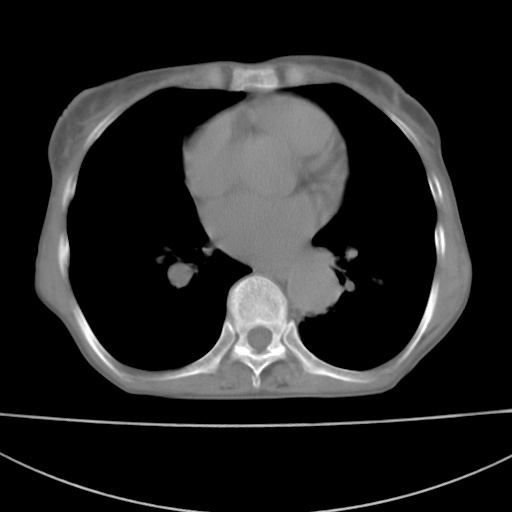

患者 女 67岁,反复咳嗽咳痰2年,加重伴喘及双下肢浮肿1月

陈旧性肺结核、慢性支气管炎、支气管扩张症、肺心症、肺动脉高压。

诸大血管及f肺门血管增粗迂曲.左下肺多发薄壁空腔影.部分非也透亮度增高.薄曾扫描可区分肺气肿类型.考虑1.慢性支气管炎 2.左下肺支气管扩张 3.肺气肿 4 肺动脉高压5.是否有先心病病史

考虑1.慢性支气管炎 2.左下肺支气管扩张 3.肺气肿 4 肺动脉高压

慢支炎、肺气肿、双肺感染、左下囊状支扩。

慢支、肺气肿、肺动脉高压;左下肺囊状支扩并粘液栓形成。